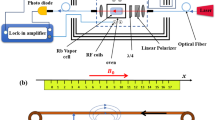

Before tracking magnetic fluid through an arterial phantom and diagnosis the stenosis location, it is necessary to identify functional properties of the atomic magnetometer in magnetic velocimetry. Thus, we desired a small ferromagnetic material with a pronounced magnetic response. Amorphous and nanocrystalline wires are the best candidates which present rectangular hysteresis loops with soft magnetic properties. So, an amorphous co-based (Co68.15 Fe4.35 Si12.5B15) microwire of particular dimensions (120 µm diameter and 1 mm length) was used in this study30,31. The permeability of the magnetic microwire is in the order of \({10}^{4}\). To stimulate the magnetization of the ferromagnetic microwire, it was subjected to a static magnetic field (4 mT) in a long solenoid with a 2 cm diameter, 36 cm length and 2500 turns. As shown in Fig. 1a, the current of the solenoid is controlled by a DC power supply.

Additionally, the magnetic microwire was placed on a belt stretching around two pulleys in order to generate a variable motion profile. Here, the drive system to build up a variable speed was a motor Gearbox controlled by a programmable DC power supply (Chroma 6104). The output of the power supply was defined via LabVIEW through GPIB interface.

Magnetic detection of this moving magnetic microwire was performed inside a three-layer µ-metal magnetic shielding based on Mx configuration of the atomic magnetometer, as displayed in in Fig. 1a32,33,34,35,36,37,38,39. This magnetometer was based on optically-detected magnetic resonance in spin-polarized 85Rb vapor which was included in an Octadecyltrichlorosilane (OTS) coated Pyrex glass cell filled with 10 torr of N2 gas. The sensing volume was defined with the cell dimensions, which was cylindrical with 2.5 cm diameter and 5 cm height. In the next procedure, Rb vapor was generated by heating the cell to around 60 °C.

A single frequency-locked by circularly-polarized beam (to the D1 transition: 794.8 nm) created spin polarization in the atomic medium and also probe the magnetization (the laser beam controlled with a loop feedback controller circuit known as a PID circuit). In this way, the medium acquired a non-isotropic distribution of magnetization called “orientation”. The magnetization interacted with the static magnetic field B0, the strength of which was described with Larmor precession frequency of \({\upomega }_{\mathrm{L}}={\upgamma }_{\mathrm{F}}\left|{\mathrm{B}}_{0}\right|\) (\({\upgamma }_{\mathrm{F}}\) is equal to ground state gyromagnetic ratio). This precession reached a steady-state magnetization under the influence of external magnetic fields and relaxation mechanisms. A weak oscillating magnetic field Brf(t) mentioned this precession coherently which was generated by a lock-in amplifier oscillator (Stanford Research Systems, SR830).

The evolution of spin polarization under the influence of the static and time-dependent magnetic fields was detected as the transmitted light intensity variates on a photodetector (2031 New Focus). This magnetometric data were extracted by phase-sensitive detection by using the lock-in amplifier signal which interfaced with a PC using a data-acquisition card (DAC). When the radio frequency was tuned near the Larmor frequency (induced by the external magnetic field), a resonance behavior was observed in the in-phase and quadrature components of the magnetometric signal (magnetic resonance signal) which have dispersive and absorptive Lorentzian dependence, respectively (Fig. 1b). Finally, the entire process of the velocity control and data acquisition was monitored and supervised by a LabVIEW program.

To detect magnetic target, the magnetometer signal was locked in the near resonance point where the dependency of the in-phase signal is linear. The resonance frequency is related to the stray magnetic field (B0) of the solenoid on the cell location that was calculated as 4250 Hz. The sensitivity of the atomic magnetometer was obtained in the order of pT by measuring its noise spectral density29. Using the phase-locked loop, we measured any variation of light intensity associated with the deviation of the frequency δf and resonance curve slope which were proportional to the magnetic field and local magnetic field gradient of the moving magnetic target, respectively29.

Experimental setup for detection of magnetic droplets

At the next step, to elucidate the role of instantaneous velocity measurements in stenosis detection, we have fabricated two artificial stenosis in an arterial phantom with different length of 7 mm and 14 mm. The phantom was a silicone tube with a 3 mm inner diameter. Small droplets of magnetic nanoparticle (Resovist (Bayer Schering Pharma) with concentration of 0.5 mmol Fe/ml) with equivalent diameter (1 mm) were generated in the tube using a programmable syringe-pump (IMSP96-1) and T-shaped inlet junction (As shown in Fig. 2). Magnetic nanoparticle droplets separated by the continuous air injection when we applied 20 mm/h flow rate for magnetic fluid phase and 600 mm/h flow rate for air phase. So, Liquid droplets generated within a gaseous flow (liquid-in-gas systems)40. The velocity of magnetic droplets is constant and slow. Therefore, the shape of the magnetic droplets doesn’t change and they don’t rotate during their movement.